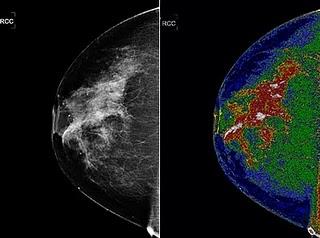

Con este nuevo instrumento, los profesionales "pueden utilizar el sistema MED-SEG para separar las imágenes de dos dimensiones en secciones relacionadas digitalmente o regiones que, después de la coloración, puede ser etiquetados individualmente por el usuario", detalla el presidente de Bartron, Fitz Walker.

Uno de los primeras aplicaciones del sistema MED-SEG, que empezará a usarse en ensayos clínicos en los próximos meses, será mejorar la mamografía. Así lo espera Molly Brewer, profesora de la División de Oncología Ginecológica de la Universidad de Connecticut, que confía en que la nueva técnica será herramienta útil para diagnosticar el cáncer de mama, reduciendo los sesgos.

Para la doctora, "la precisión del MED-SEG permite al médico ver muchos más detalles y de mejor calidad lo que podría ahorrar a los pacientes una gran cantidad de pruebas costosas e innecesarias".